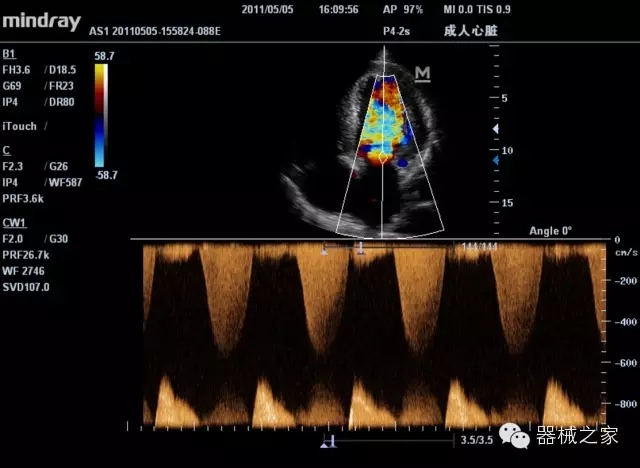

經(jīng)典產(chǎn)品:M7(星鉆)

臨床圖片賞析

產(chǎn)品特點

·裝載有采用Multi-Core多核處理的非嵌入式平臺,成像效率大大提高,并且能夠給用戶帶來高速、多任務(wù)并行信號處理體驗;

·優(yōu)秀的圖像效果、強大的功能體驗、豐富的探頭選擇、合理的便攜式設(shè)計,全中文顯示及病人管理界面,使得M7在任何場合、任何時候都能快速響應(yīng)更好的心血管、腹部、婦產(chǎn)、小器官等常規(guī)超聲檢查以及肌骨、神經(jīng)、顱腦、術(shù)中等新興領(lǐng)域的使用需求;

8倍波束并行處理系統(tǒng)

·在便攜式緊湊平臺上采用更多倍波束并行接收信號處理模式,無論二維還是彩色血流圖像狀態(tài)下,擁有更靈敏的回波頻移捕獲能力,大大提高時間分辨率,尤其使得心血管表現(xiàn)更為突出;

PSHI?寬帶頻移諧波技術(shù)

·在普通組織諧波的基礎(chǔ)上,通過精確控制的波束形成器,發(fā)射兩組具有相位偏差反向的信號,并采用并行信號處理,數(shù)字化合成并采樣回波信號,在高靈敏度的濾波器的處理過程中獲取更純凈的諧波信號,使圖像具有更加出眾的細節(jié)分辨率;

iClear®+iBeam?

·智能化按線復(fù)合多角度獲取聲束的原始信號,配合智能化的斑點噪聲識別及控制處理技術(shù),整體提高組織結(jié)構(gòu)細節(jié)分辨率,任何時候都能快速響應(yīng),更好的滿足心血管的使用需求;

支持全新3T工藝探頭群

·包括探頭材料、結(jié)構(gòu)設(shè)計、加工工藝三方面的革新技術(shù)給圖像帶來品質(zhì)的飛躍;